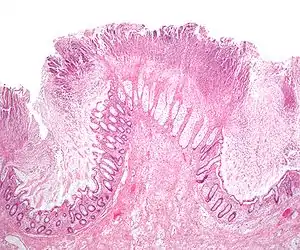

Micrograph of pseudomembranous colitis, an indication for colectomy. H&E stain.